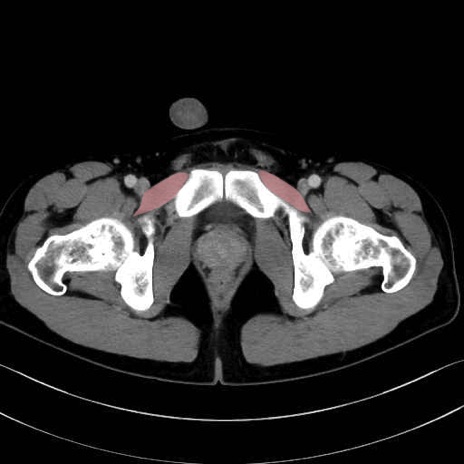

恥骨筋 (Pectineus)

長内転筋 (Adductor longus)

短内転筋 (Adductor brevis)